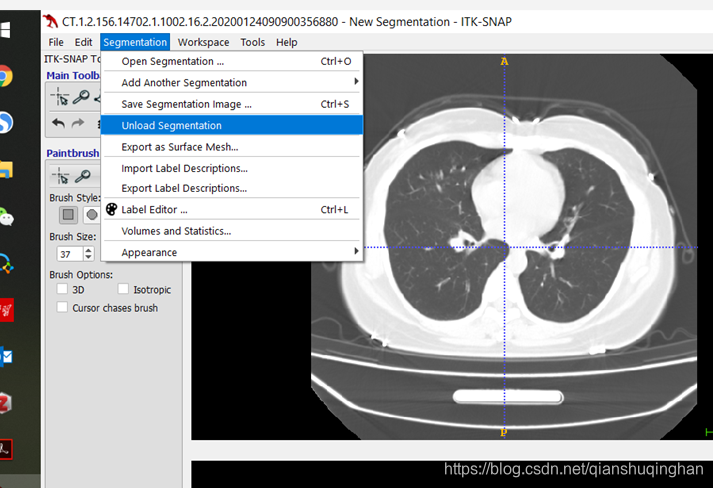

载入此前标注的mask文件

从菜单栏Segmentation->Upload Segmentation 选择mask文件载入;

从菜单栏Segmentation->Save Segmentation Image ... (此前无标注结果) or

此前有标注结果:Save “Untitled.nii.gz”(直接覆盖)or 另存为Save “Untitled.nii.gz” as ... 保存为其他文件

可选为标注结果的文件类型和保存位置